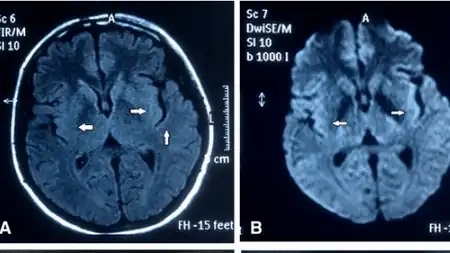

Studies have shown subtly decreased metabolism on positron emission tomography (PET) and single photon emission computed tomography (SPECT) in the left inferior frontal and left temporal lobes.[9] and or basal ganglia hypermetabolism.[8] Ancillary laboratory tests including MRI and brain biopsy have confirmed temporal lobe involvement. Cranial MRI shows increased signal in the hippocampus.[10]